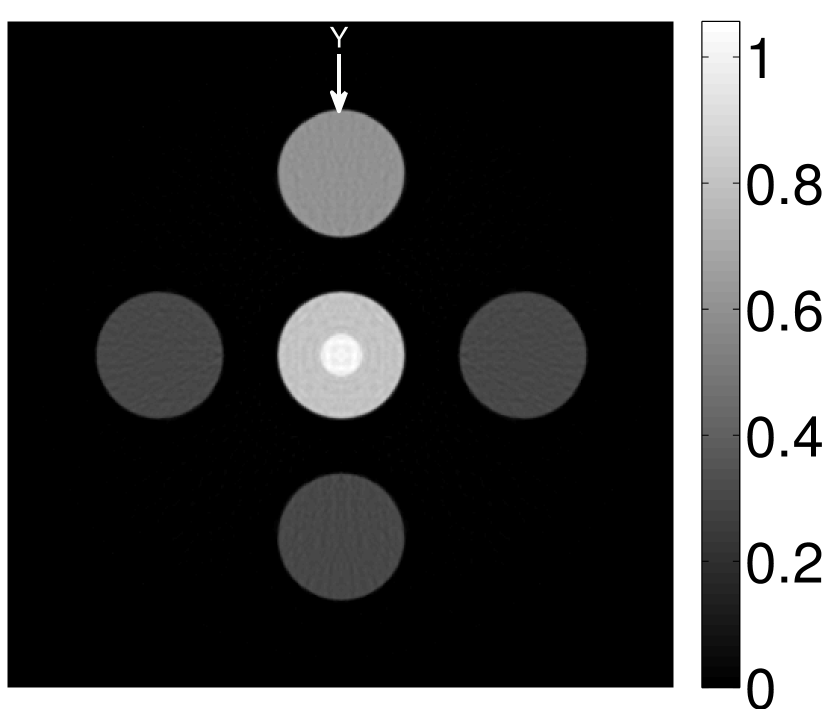

The numerical phantom shown in Figure 1(a) was employed. The phantom had a support area of mm2 and contained six uniform disks that were assigned different values of absorbed optical energy density.

Figure 2(a) shows the image reconstructed by use of the conventional iterative method that utilized a system matrix based on EIR-2. Different values of the regularization parameter from the interval were considered. The reconstructed image with the value of that minimized the RMSE was chosen to represent the best performance of the conventional iterative method. Figure 2(a) and the profile in Figure 2(c) demonstrate that the use of an inaccurate EIR can result in strong artifacts and distortions in images reconstructed by use of the conventional methods.

When the VP algorithm was applied, different values of the regularization parameter from the interval and from the interval were considered. The image that minimized the RMSE was chosen and displayed in Figure 2(b). As revealed by this image and the profiles in 2(c), the VP algorithm yielded an image with fewer artifacts and distortions, and image fidelity was improved as reflected by the reduced RMSE.